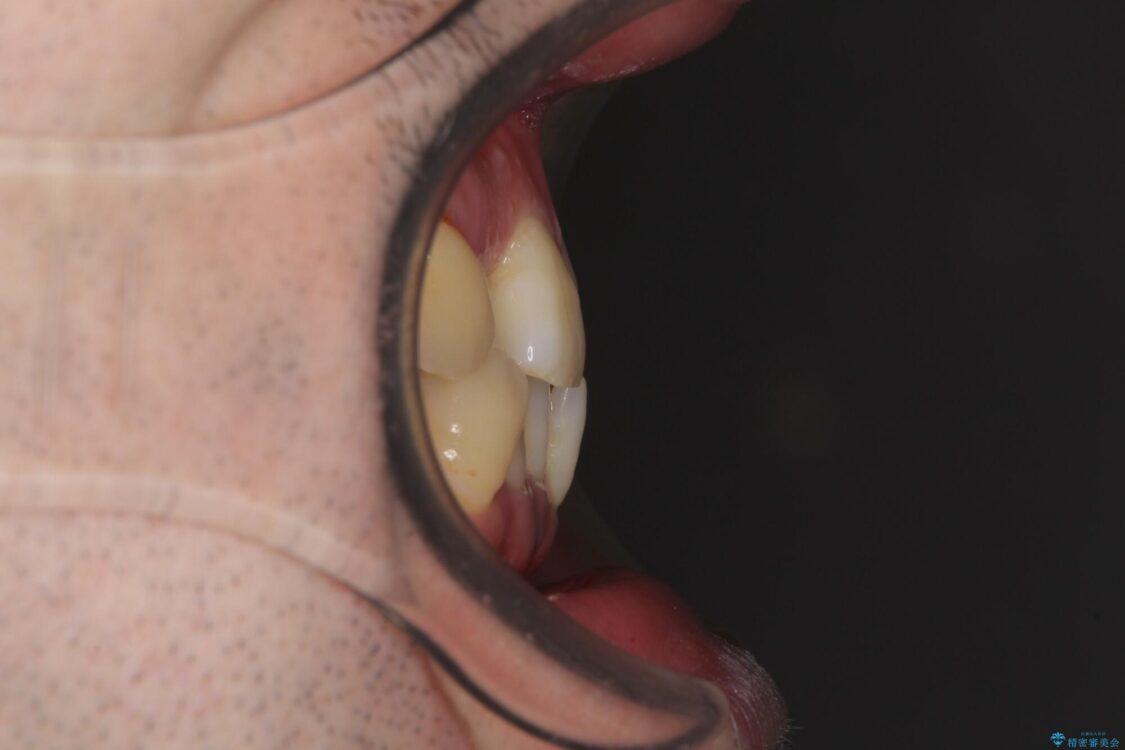

治療途中

• 割れてしまった奥歯とデコボコの前歯 矯正治療とインプラント治療 治療途中画像